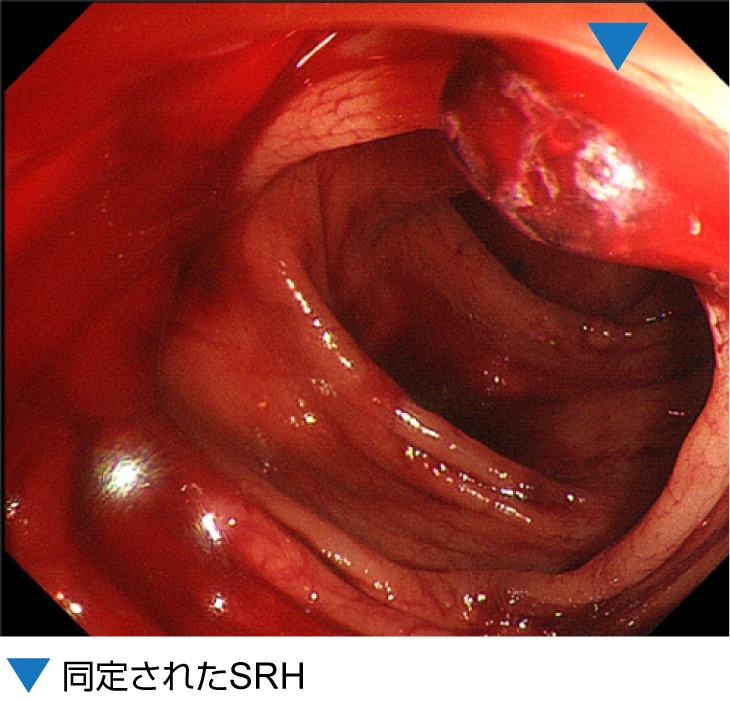

大腸憩室出血の下部消化管内視鏡画像

上行結腸の憩室内にSRHと多量の凝血塊を認める。